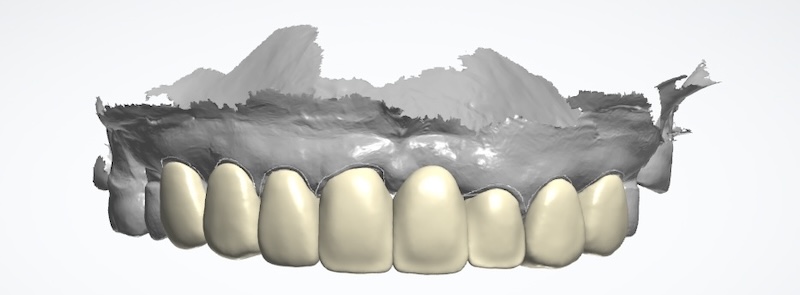

全鋯冠牙橋搭配全瓷貼片,解決前牙牙縫大

牙周治療過後的美容重建才是高難度的任務。幸好我們現在有數位化的輔助,能夠在還沒修牙齒、做假牙之前,就先讓患者初步試戴(mock up),體驗看看未來完成時的外貌。此時患者也能回饋自己的想法讓醫師和牙技師暸解,輔助我們在合理的範圍內修改到患者能接受的樣子。

討論定案後,我會依照共同決定的結果來修型,口內掃描後再由數位牙技師進行數位化電腦設計與製作。上顎牙橋是使用全鋯冠,其他牙齒則都使用全瓷貼片,將整體空間做好協調分配,完成之後順利地把所有牙縫幾乎都成功關閉。

試戴流程利用複合樹脂置放在牙齒上,和患者溝通外型。如果有出現比較黃的牙齒顏色,代表牙齒本身位置比較突,這種情況牙齒會需要修得比較多一些,未來才有辦法同時改變牙齒的顏色和視覺上的排列位置:

由這個例子來看,當患者的牙齒位置不佳,雖然理想上矯正治療是牙醫師會優先建議的方案,並且一般而言,矯正過後再做美容牙科的貼片療程,能減少牙齒修磨量。

以上這些情況,我會建議好好評估一下數位美容重建流程,也可以達到很不錯的效果。